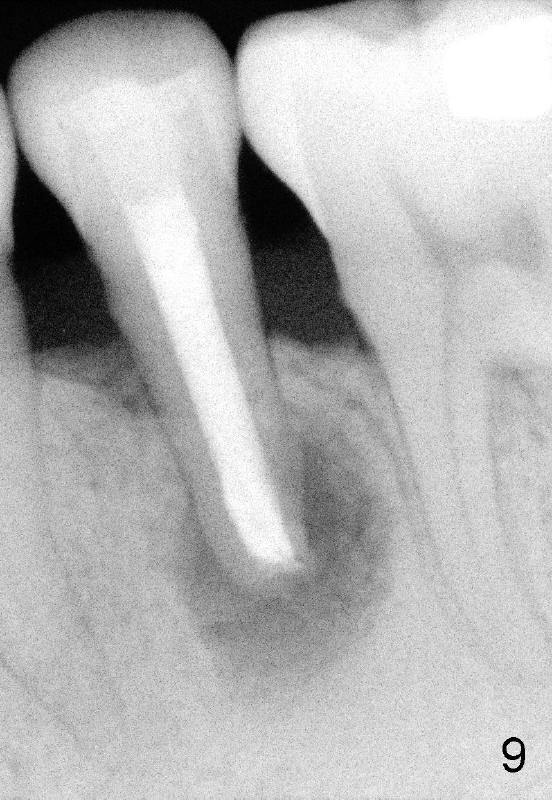

A 40-year-old Chinese man has periodic (once a month) mild pain and swelling in the lower left quadrant. Clinical exam reveals dens evaginatus (Fgi.1': <) in #20. Upon pressure from mouth mirror handle, there is limited amount of purulent discharge from the fistula (Fig.1": <). Preop PA shows a large canal with large periapical radiolucency (Fig.1). RCT started on Aug 6, 2010 with #70 file at 20 mm (Fig.2), #120 file at 16 mm (Fig.3) and CaOH paste in the canal (Fig.4). The dressing changed on Oct 8, 2010 (Fig.5). RCT finished on Jan 25, 2011 with master cone (rolled with several gutta perchae) (Fig.6), lateral condensation (Fig.7) and after vertical condensation and build-up (Fig.8). The canal was wet in the last two appointments with no sign of apexification. Follow up is done in 7 months (Fig.9), 11 months (Fig.10) and 18 months. Although the patient reports no pain after the treatment, the fistula remains with purulent discharge. The patient does not accept apical surgery. What should we do? Retreat with MTA (1,2,3)?